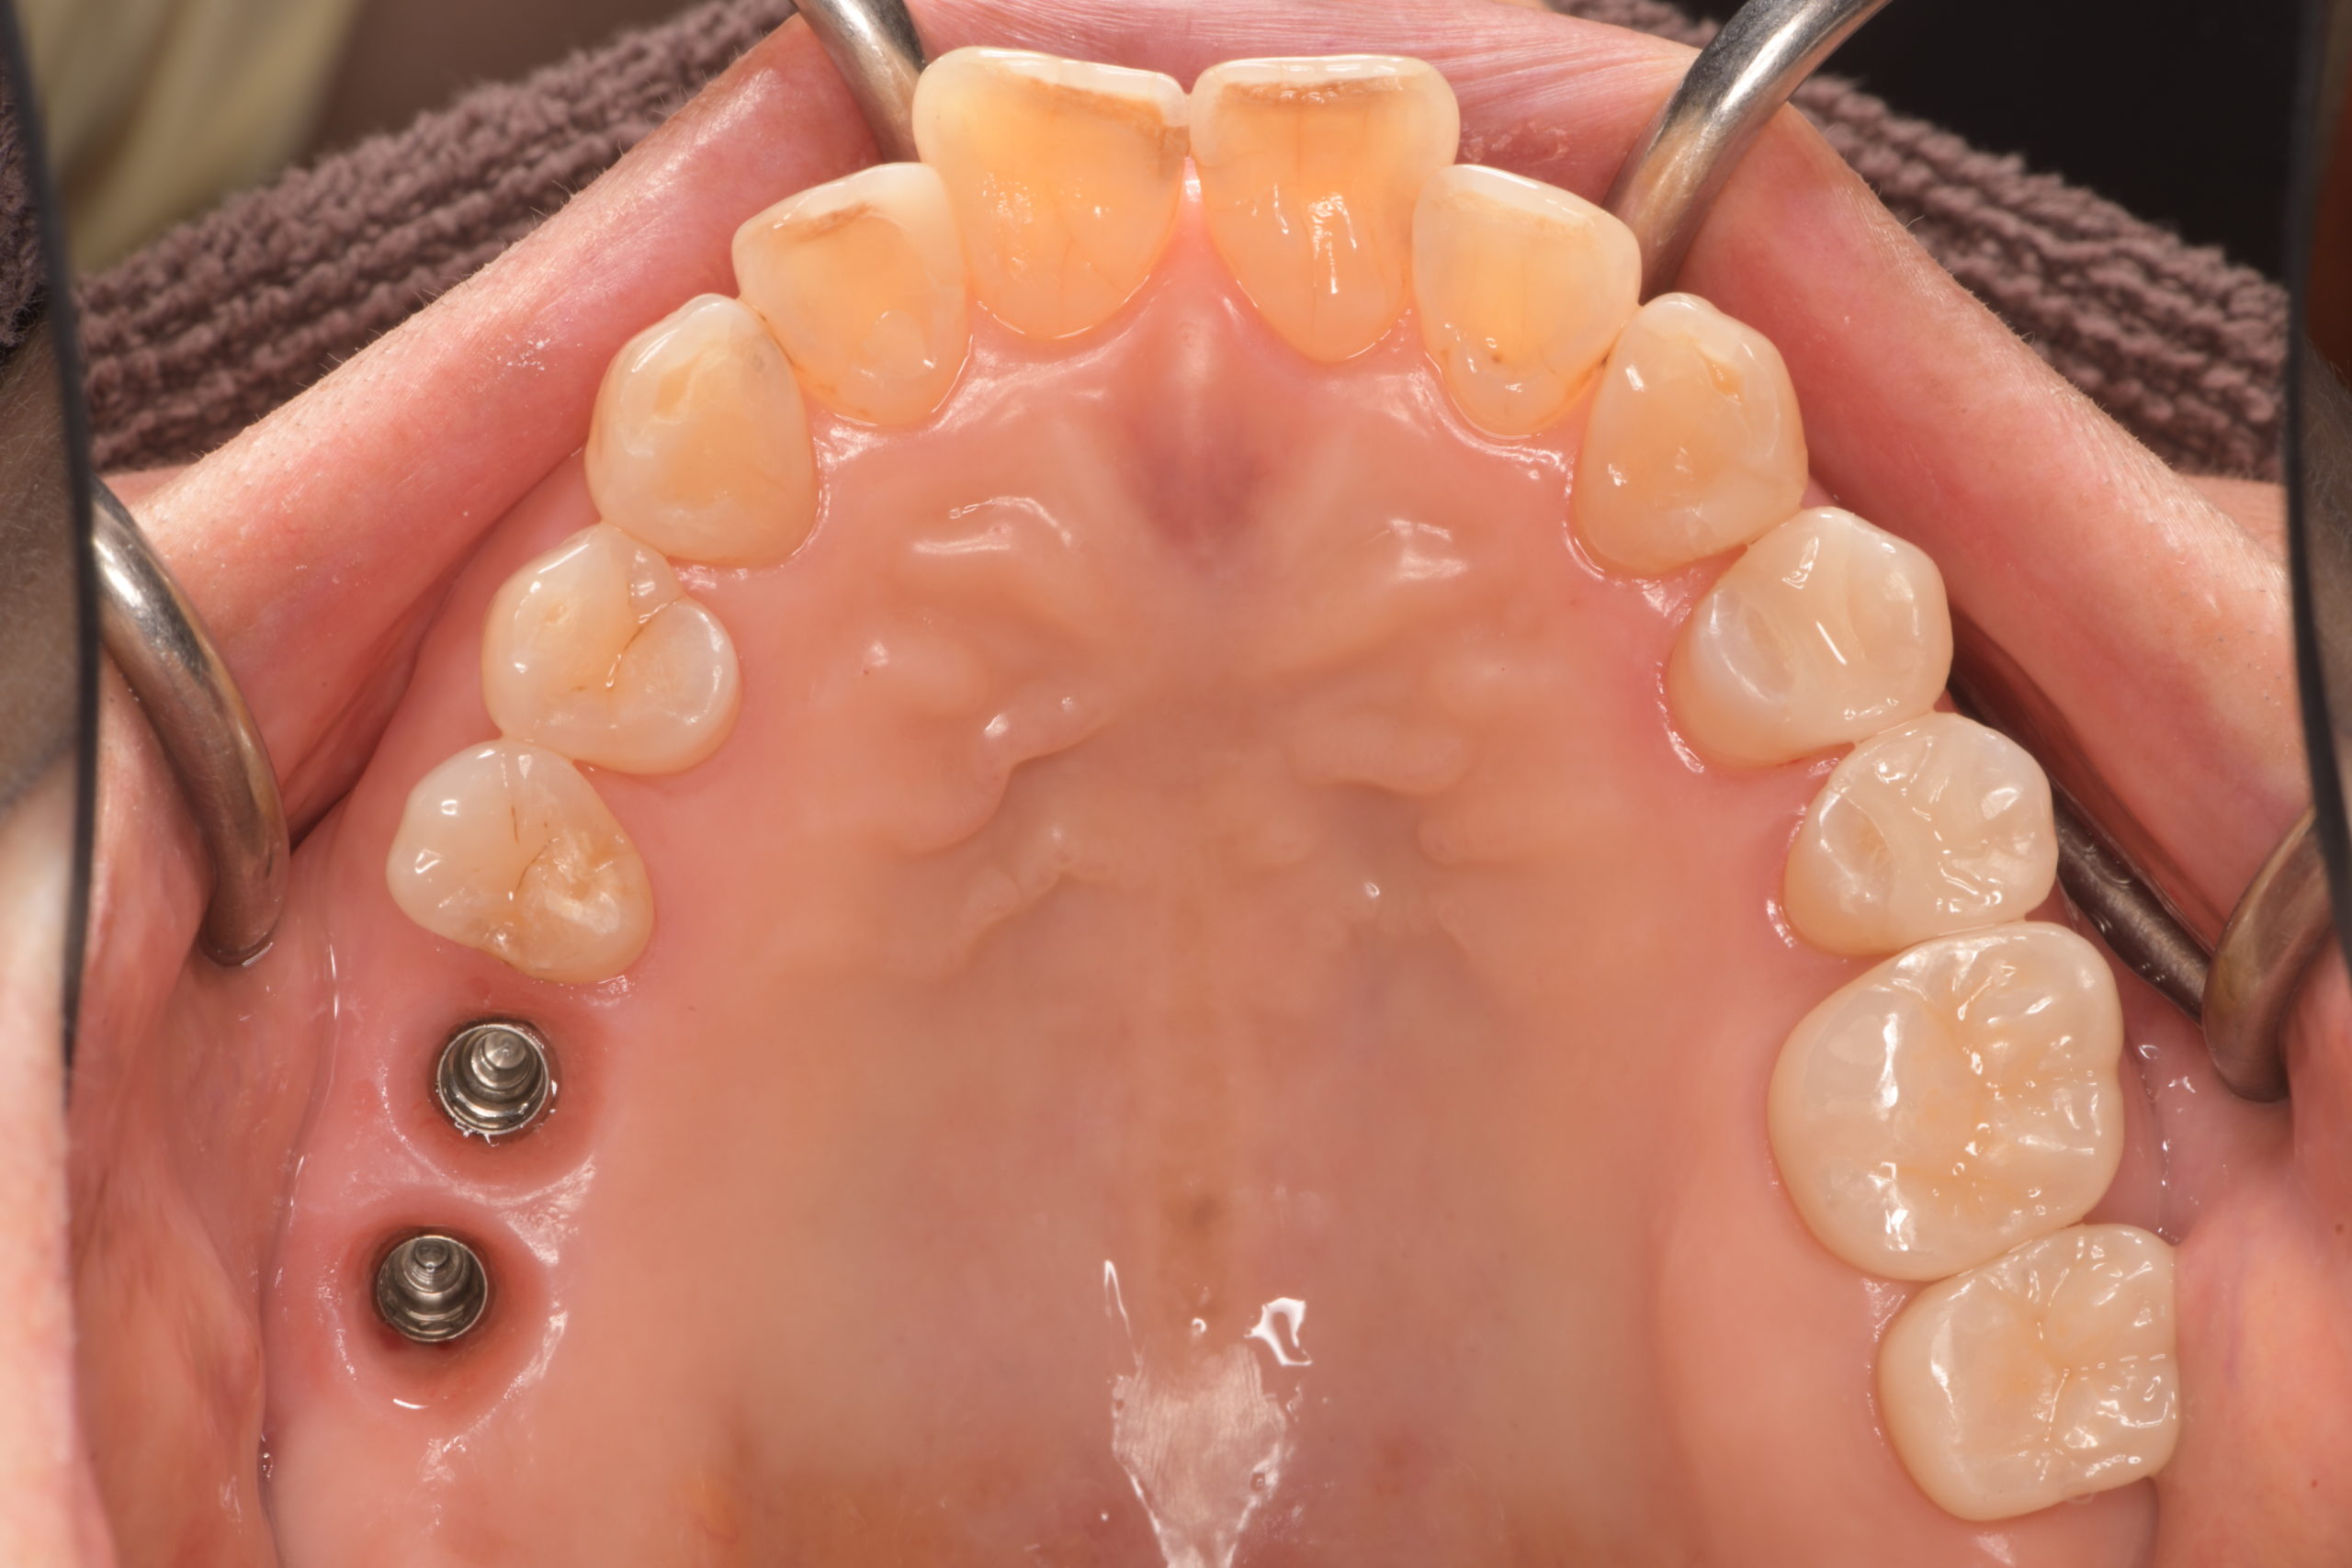

上顎臼歯部インプラント治療前

上顎臼歯部インプラント上部構造装着前

上顎臼歯部インプラント治療完了